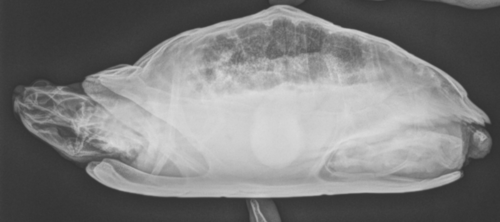

Для начала надо сделать цифровой рентген. В каких проекциях надо сделать, чтобы определить причины ? Или лучше все 3. С живота, профиль и сверху (черепашка головой вверх). И какие есть нюансы, чтобы врачу сообщить.

в идеале в 3х проекциях, настройки обычно  67кВ на 2мА/сек, также допустимо 50кВ на 6-8мА/сек

Похоже в моем случае все куда хуже и серьёзнее (((

Из того, что я вижу - у черепахи каловый завал или вообще непроходимость и уменьшен объем лёгких. Создать для Вас тему? Может помогут найти хорошего очного врача в Туле.